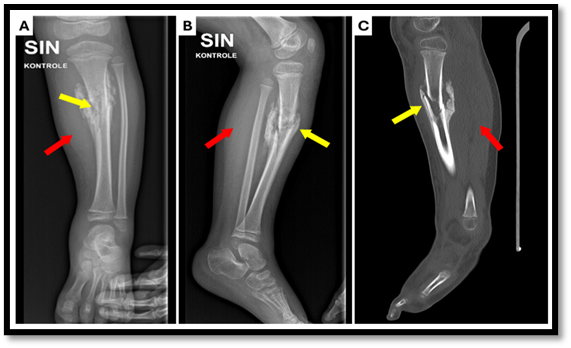

Fig. no4: (A) X-ray anterior–posterior projection

(B) X-ray lateral projection

(C) computed tomography (CT) scan of the lower left leg.